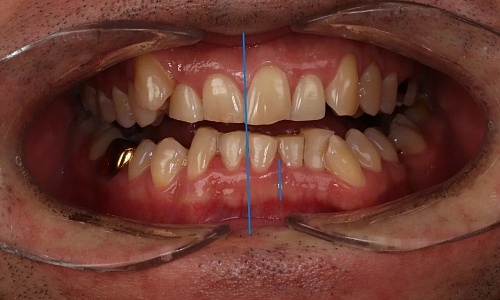

до

после

Протезирование керамическими винирами на естественных зубах и коронками на имплантах

Стоматолог-ортопед на Ленина 12